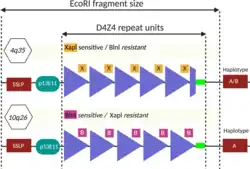

D4Z4 repeat array types are subclassified into 4qA and 4qB alleles, with only 4qA alleles causing disease. 4qA alleles are defined by a specific sequence of DNA immediately downstream to the D4Z4 repeat array: a 260 base pair region named pLAM, followed by a 6,200 base pair beta satellite region.[9][59] 4qA and 4qB alleles, together, can be subdivided into at least 17 types,[51] based on the DNA upstream from the D4Z4 repeat array, the presence/absence of restriction enzyme sites within D4Z4, the size of the last D4Z4 repeat element, and the DNA present downstream to the D4Z4 repeat array.[59] For example, the most common 4qA allele, 4A161, has 161 nucleotides in the region upstream from the D4Z4 repeat array,[27] and can, in turn, be subdivided into 4A161S and 4A161L (short and long), which are characterized by a flanking D4Z4 repeat units of 300 nucleotides and 1,900 nucleotides, respectively.[59]

Restriction fragment length polymorphism (RFLP) analysis was the first genetic test developed and is still used as of 2020, although it is being phased out by newer methods. It involves dicing the DNA with restriction enzymes and sorting the resulting restriction fragments by size using southern blot. The restriction enzymes EcoRI and BlnI are commonly used. EcoRI isolates the 4q and 10q repeat arrays, and BlnI dices the 10q sequence into small pieces, allowing 4q to be distinguished.[4][51] The EcoRI restriction fragment is composed of three parts: 1) 5.7 kb proximal part, 2) the central, variable size D4Z4 repeat array, and 3) the distal part, usually 1.25 kb.[92] The proximal portion has a sequence of DNA stainable by the probe p13E-11, which is commonly used to visualize the EcoRI fragment during southern blot.[51] The name "p13E-11" reflects that it is a subclone of a DNA sequence designated as cosmid 13E during the human genome project.[93][94] Considering that each D4Z4 repeat is 3.3 kb, and the EcoRI fragment contains about 5 kb of DNA that is not part of the D4Z4 repeat array, the number of D4Z4 units can be calculated.[78]

- D4Z4 repeats = (EcoRI length - 5) / 3.3

Sometimes 4q or 10q will have a combination of D4Z4 and D4Z4-like repeats due to DNA exchange between 4q and 10q, which can yield erroneous results, requiring a more detailed workup.[51] Sometimes D4Z4 repeat array deletions can include the p13E-11 binding site, warranting use of alternate probes.[51][95]